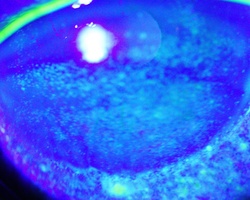

- ドライアイは眼表面が涙液で十分に覆われないため,眼球が乾燥し,眼球表面に傷がついたり,瞬目(まばたき)の時に眼瞼との摩擦が増え,様々な症状を来します。